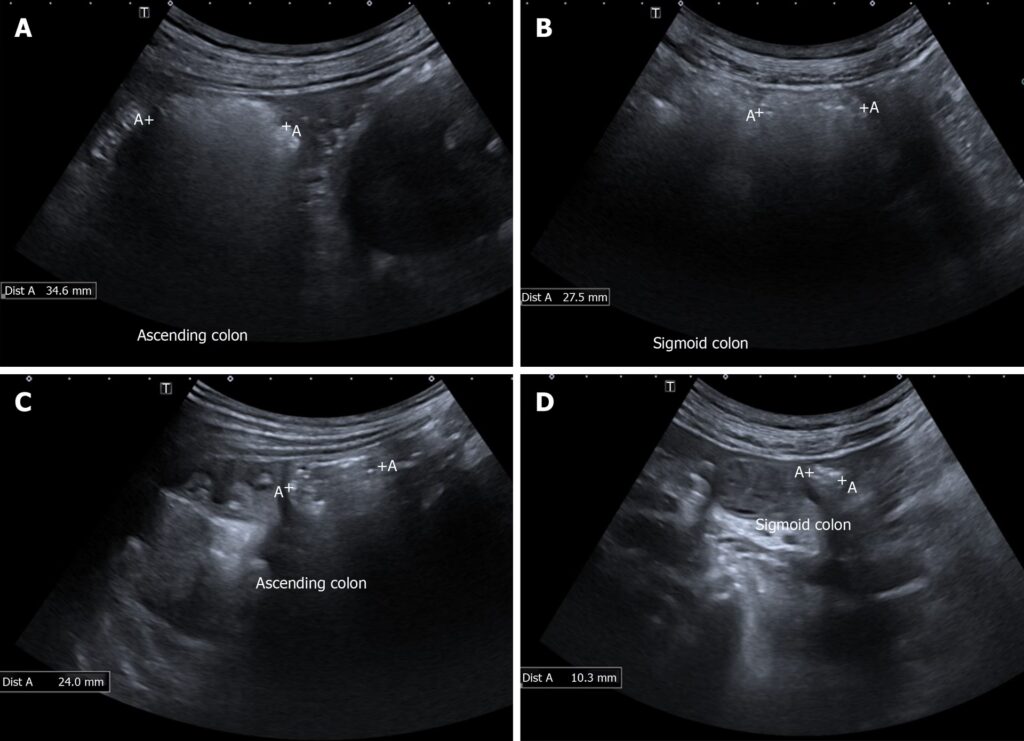

Forskere har længe teoretiseret, at IBS er forbundet med en unormal motilitet (bevægelse) i tarmen og usædvanligt høje tryk, især i den sidste del af tyktarmen, kendt som sigmoid colon eller den slyngede tyktarm. Ligesom enhver anden muskel i kroppen, der udsættes for kronisk overbelastning, antog man, at muskelvæggen i tarmen kunne blive tykkere (hypertrofi) som reaktion. Da sigmoid colon ligger tæt på de kvindelige kønsorganer, opstod ideen om at bruge transvaginal ultralyd – en almindelig gynækologisk undersøgelse – til at visualisere og måle tykkelsen af denne tarmdel.

Et studie undersøgte 175 kvindelige patienter, der skulle have en almindelig gynækologisk ultralydsscanning af forskellige årsager, såsom smerter, cyster eller blødningsforstyrrelser. Ingen af dem blev henvist specifikt på grund af tarmproblemer. Under hver scanning målte lægerne tykkelsen af muskelvæggen i patientens sigmoid colon. Først efter målingen var foretaget, blev patienterne spurgt, om de tidligere var blevet diagnosticeret med IBS.

Resultaterne var slående. Ud af de 175 kvinder havde 27 en bekræftet IBS-diagnose. Hos kvinderne uden IBS var den gennemsnitlige tykkelse af muskelvæggen 1,9 mm. Hos kvinderne med IBS var den gennemsnitlige tykkelse næsten dobbelt så stor: 3,6 mm. Denne forskel var statistisk yderst signifikant.